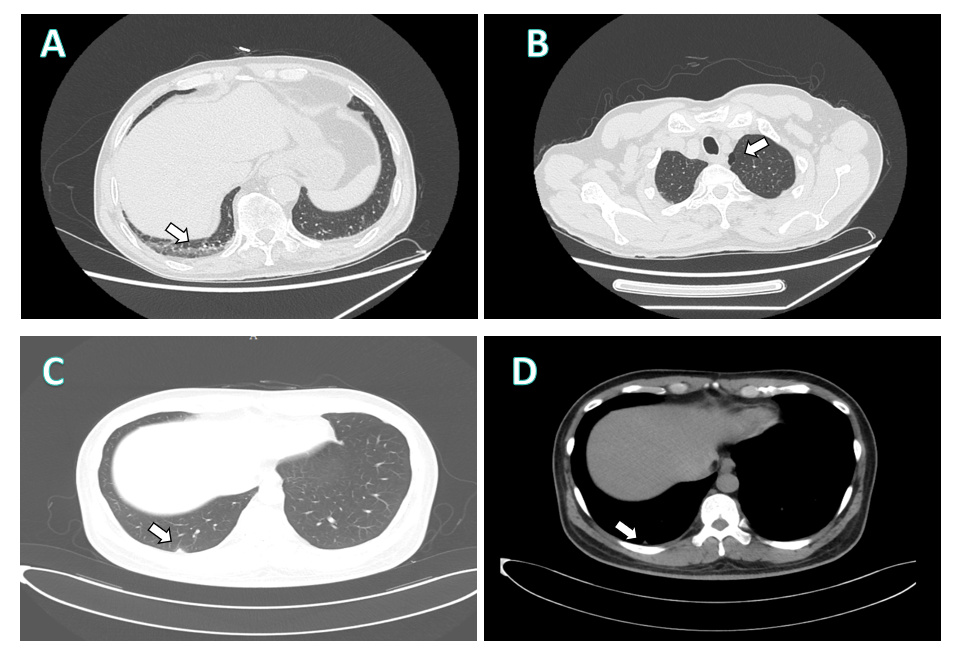

转院后,患者体温37.6℃,脉搏78次/min,呼吸24次/min,血压147/77 mmHg,精神欠佳,后背及左肩有散在出血点,其余皮肤、黏膜无瘀点、瘀斑。四肢湿冷,双下肢明显水肿。查血常规:WBC 2.1×109/L,LY% 13.6%,GR% 84.2%,MONO% 2.2%,PLT 46×109L-1,hs-CRP13.2 mg/L。肝肾功能:ALT 89 U/L,AST 191 U/L,CREA 111. 9 mmo1/L,GGT 119 U/L,CK 565.0 U/L,BUN 11.57 mmo1/L,GLU 8.59 mmo1/L,ALB 30.2 g/L,GLOB 32.9 g/L,Na+ 128.2 mmo1/L, Ca2+ 1.86 mmo1/L,LDH 691.0 U/L。凝血功能:D-dimer 7.40 mg/L,TT 31.7 s,APTT 46.1 s。胸腹部CT:两肺上叶局限性肺气肿,两肺下叶胸膜下少许片絮影(图 1),食管下段管壁增厚伴周围小淋巴结,建议胃镜检查;腹膜后及双侧腹股沟区结节样淋巴结(右侧稍大)。心脏彩超:左房室内径正常,左室壁不增厚,静息状态下各节段收缩活动减弱,左室EF为47%。急查NGS提示新型布尼亚病毒核酸阳性。SOFA评分为2分(意识改变,呼吸频率 > 22次/min)。给予监护、床边隔离,并随即进行抗病毒(法韦拉韦)、抗感染(多西环素)、升血小板、升白细胞,护胃、营养支持等对症治疗。入院2 d后患者凝血障碍加重,予补充凝血因子,输注凝血酶源复合物等治疗。肝肾功能持续恶化,入院5 d后,ALT 2 944 U/L,AST 7 500 U/L,CREA 280.1 mmo1/L。心脏、呼吸、循环均进行性衰竭,血压难以维持,经抢救无效死亡。最后诊断为:①发热伴血小板减少症(新型布尼亚病毒感染);②脓毒性休克;③多器官功能衰竭(肝脏、肾脏、呼吸、凝血);④冠状动脉粥样硬化性心脏病(PCI术后),心功能Ⅱ级。

| 图 1 两名病例CT检查结果。A:(病例1)右下叶胸膜下可见少许片絮影(箭头所示);B:(病例1)左肺上叶可见局限性肺气肿(箭头所示);C-D: (病例2)右肺下叶胸膜下结节,周围见少许磨玻璃影,边界欠清(箭头所示) |

病例2为中年男性,44岁,为病例1的主治医生。在抢救病例1的过程中,全程佩戴医用手套和口罩,穿戴隔离衣,但未佩戴医用护目镜。在做ECMO操作时,病例1有血液喷溅在隔离衣上,但未有直接接触。在对病例1气管插管及断开呼吸机吸痰时,有气溶胶接触的过程。病例2与病例1接触10 d后,于2024-06-18出现发热,最高体温39.5℃,极度乏力,腹泻,无胸闷胸痛,无咳嗽、咳痰,无恶心、呕吐。2024-06-24血常规:WBC 1.5×109L-1,LY% 24.6%,GR% 69.4%,PLT 91×109/L,HGB 140 g/L,CRP 1.6 mg/L。肝肾功能示:ALT 53 U/L,AST 67 U/L,GGT 46.2 U/L, CREA 94.3 mmo1/L,CK 291.4 U/L,ALB 36.6 g/L, GLOB 23.5 g/L,BUN 5.19 mmo1/L,GLU 10.36 mmo1/L,LDH 333.5 U/L, Na+ 133.3 mmo1/L, Ca2+ 2.0 mmo1/L。予玛巴洛沙韦治疗后未见明显好转。2024-06-25因“发热7 d”入院。查体:体温38.3℃,脉搏89次/min,呼吸20次/min,血压128/78 mmHg,神志清晰,面色潮红,结膜充血,全身皮肤未见异常,口唇无发绀,双肺呼吸音粗,未闻及干湿啰音,心率89次/min,律齐,腹平软,全腹无压痛反跳痛,四肢肌力张力正常,有肌肉颤动,双下肢无水肿。给予法维拉韦抗病毒,甲基强的松龙80 mg减轻炎症反应,丙种球蛋白提高免疫功能。入院1d后,查血细胞分析:WBC 7.0×109/L,LY% 12.2%,GR% 80.8%,HGB 158 g/L,HCT 45.2%,hs-CRP < 0.5 mg/L,PLT 94 ×109/L。肝肾功能:ALT 225 U/L,AST 91 U/L,CREA 72.7 mmol/L,BUN 3.72 mmol/L,CK 5 272.0 U/L,GGT 51 U/L,CK-MB 35.6 U/L,ALP 56 U/L,LDH 1 208.0 U/L,TP 68.6 g/L,ALB 36.7 g/L,GLOB 31.9 g/L,GLU 12.01 mmol/L。凝血常规:D-dimer 1.59 mg/L,INR 0.98,PT 11.30 s,APTT 43.3 s, TT 23.9 s,FIB 2.588 g/L,SF > 2 000.00 ng/mL, BDG 1 414.0 pg/mL。胸部CT提示右肺下叶胸膜下结节,周围见少许磨玻璃影,边界欠清(图 1)。给予还原型谷胱甘肽保肝,辅酶Q10营养心肌,伏立康唑抗真菌,乌司他丁抗炎症介质处理。查NGS及核酸检测均提示新型布尼亚病毒感染。立即转入隔离病房,治疗10 d后,除血清铁蛋白偏高,为1 301.41 ng/mL,其余指标均明显好转,生命体征平稳。出院诊断:①发热伴血小板减少症(新型布尼亚病毒感染);②脓毒症;③多器官功能损伤(肝脏、心肌)。本研究已通过医院伦理委员会批准。